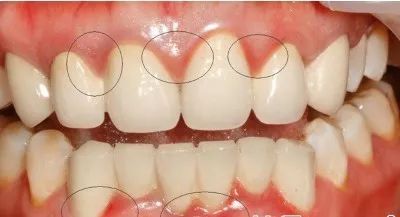

牙周炎

智齿地处腮帮子和牙床的交界处,很多时候周围已经不是坚韧的牙龈组织,而是松软的粘膜组织,抵抗力低下,非常容易发生牙周炎。

不管是龋齿还是牙周炎,都是细菌导致的“传染性”疾病,会有源源不断的致病菌从智齿向口腔内其它牙齿播散,其中受累最重的就是毗邻的第二磨牙。